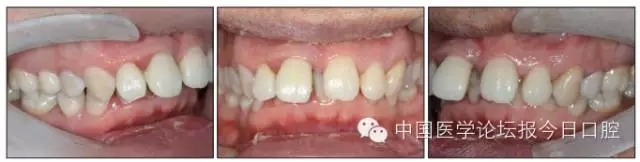

口內(nèi)情況:恒牙列,24、34、44缺失,磨牙Ⅲ類關(guān)系,上牙列散隙,上前牙扇形漂移。前牙深覆(牙合)、深覆蓋??谇恍l(wèi)生較差,11與12間牙齦乳頭紅腫,多個(gè)牙探診有牙周袋形成,11松動(dòng)Ⅰ度,余切牙松動(dòng)(-),患者面像及口內(nèi)像如圖1、2所示。

圖2 治療前口內(nèi)像